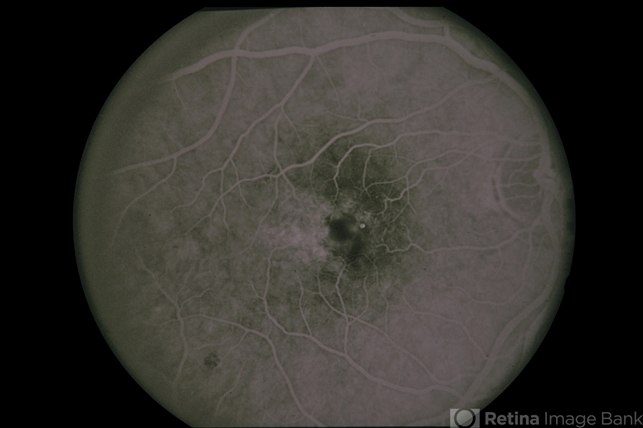

Juxtafoveal Telangiectasis / DM / Diabetes

Juxtafoveal Telangiectasis DM Diabetes

juxtafoveal telangiectasis, diabetic maculopathy, diabetes

37-year-old white female, juxtafoveal telangiectasis / DM / diabetes.